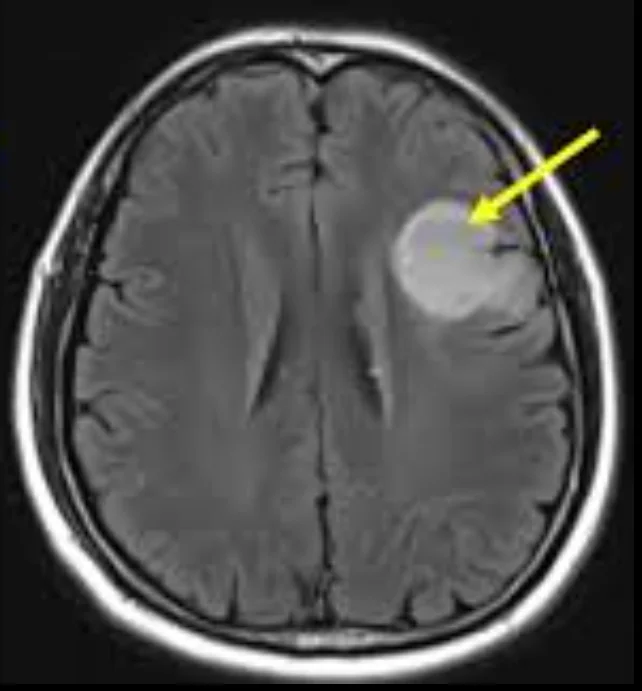

The diagnostic journey usually begins with a contrast-enhanced MRI scan, which provides detailed images of the brain and helps doctors assess the tumor’s size, location, and behavior.

- Glioblastoma often appears as an irregular, aggressive-looking mass. It typically shows uneven contrast enhancement, significant surrounding brain swelling (edema), and dark central areas that represent dead or necrotic tissue. These features suggest rapid growth and infiltration into nearby brain tissue.

- Lower-grade gliomas, on the other hand, usually look more uniform and well-defined. They tend to grow more slowly, cause less swelling, and often lack areas of tissue death. Some may not enhance strongly with contrast at all.

While MRI provides strong clues, imaging alone cannot confirm the exact tumor type or grade.